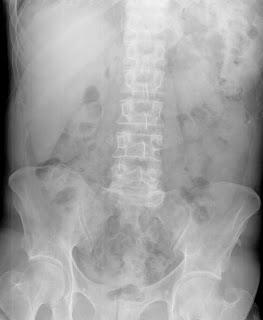

El lóbulo hepático de Riedel es una variante anatómica en la cual hay una prolongación hepática derecha en forma de lengüeta o punta de lanza que abarca el flanco derecho y puede llegar incluso hasta la cresta iliaca. El lóbulo de Riedel puede ser un hallazgo al examen físico y podría confundirse con una hepatomegalia. También aparece descrito en Rx de abdomen como en la imagen del artículo o durante la ecografía abdominal.En pacientes sanos el diagnostico es muy fácil pero cuando hay enfermedad o alteraciones de la función hepática la presencia del lóbulo de hepático de Riedel puede llevar a realizar pruebas innecesarias ante la sospecha de un crecimiento hepático. Lo que habitualmente nos ayuda a diferenciarlo es su forma característica.

No hay problemas de la salud asociados a tener una variante hepática de Riedel a excepción del hecho de tener parénquima hepático por debajo del reborde costal, sin protección, podría favorecer hematomas hepáticos en casos de traumatismos abdominales.